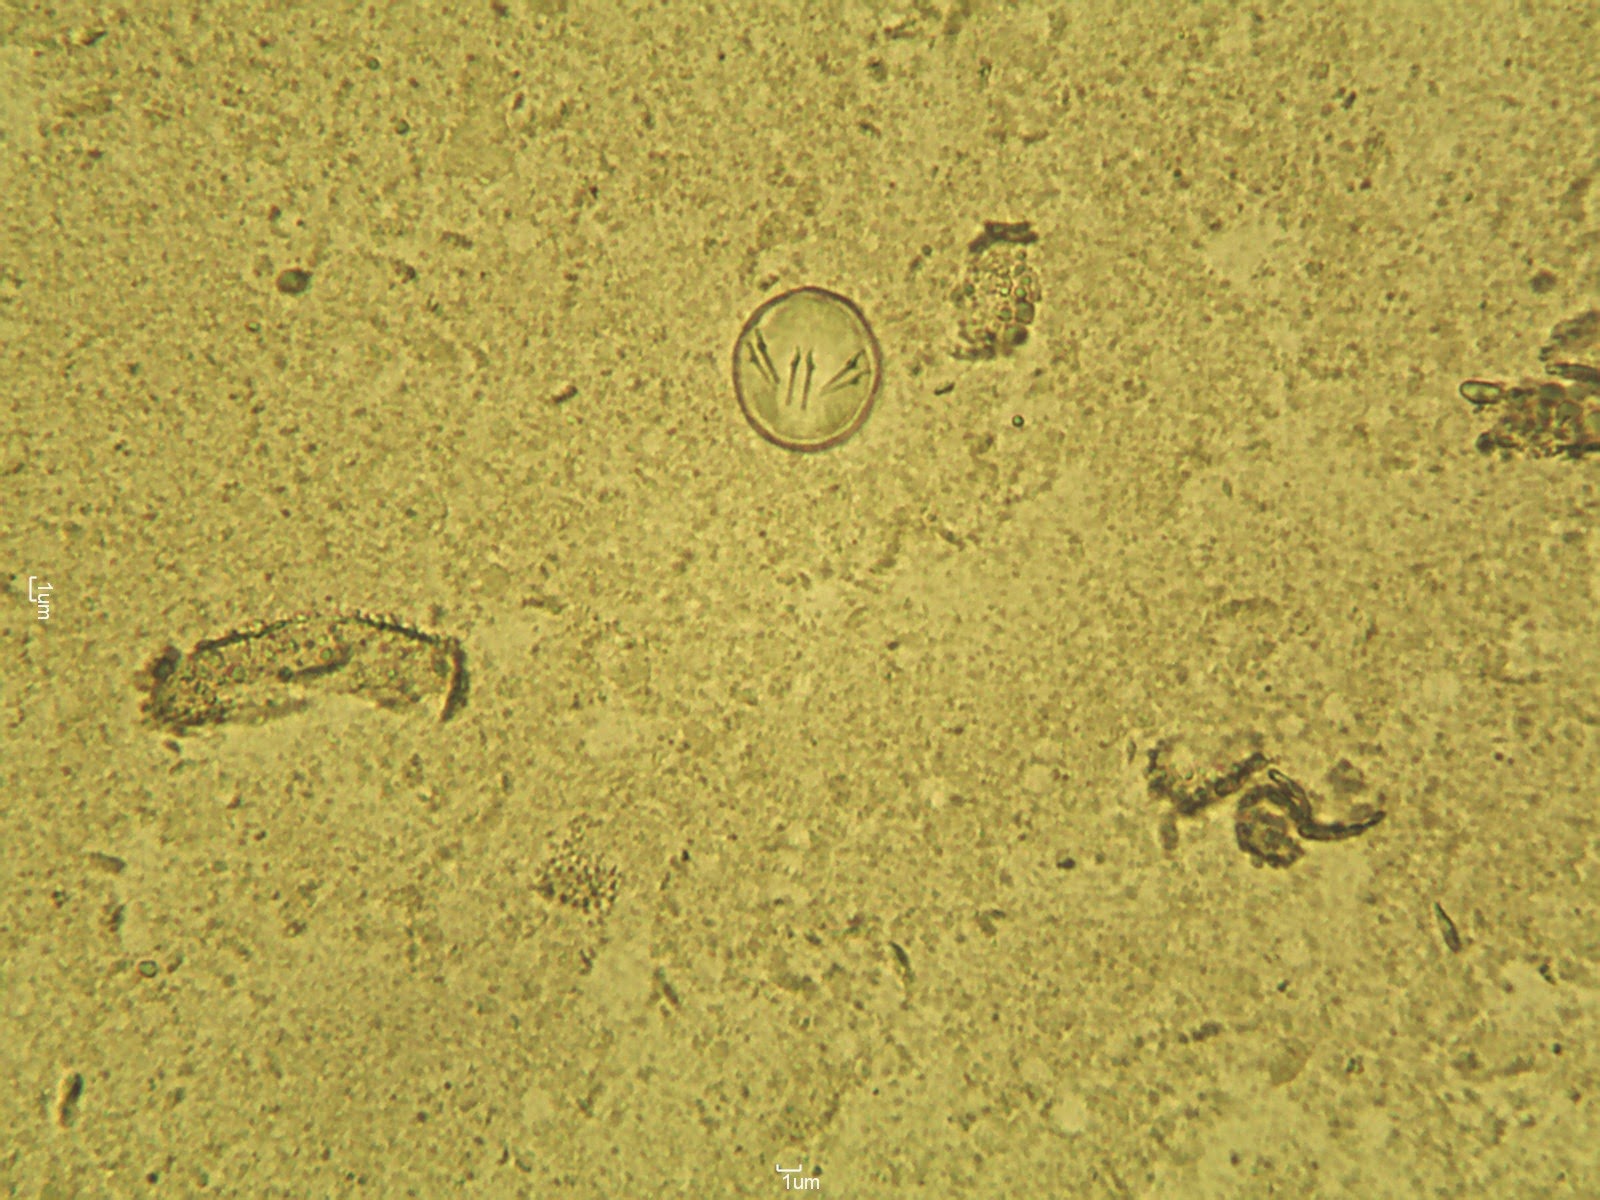

Tapeworms Worms In Cat That Look Like Rice Or Sesame Seeds Mack Packing

Tapeworm Infection In Dogs Vca Animal Hospital